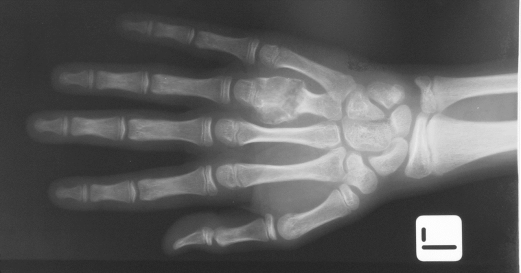

Enkondrom

Enkondrom kemik medullasına yerleşen, kıkırdak üreten selim tümördür. Genellikle ikinci dekatta görülmesine karşın her yaş grubunda rastlanabilir. Genellikle uzun kemiklerde ve el kemiklerinde santral yerleşir. El ve ayakta en sık görülen tümördür. Bulgular yerleşime ve lezyonun yayılımına göre değişir. Kırık gelişmez ise asemptomatiktir. Rastlantısal olarak çekilen grafilerle tespit edilir. Kırık olmadan ağrı olursa düşük dereceli kondrosarkom için ayırıcı tanıya gidilmelidir. Tek enkondrom olgularında çekilen grafilerle kontrol yapılmalıdır. Lezyonda bir değişiklik yok ise müdahaleye gerek yoktur. Enkondrom soliter veya multiple olabilir.